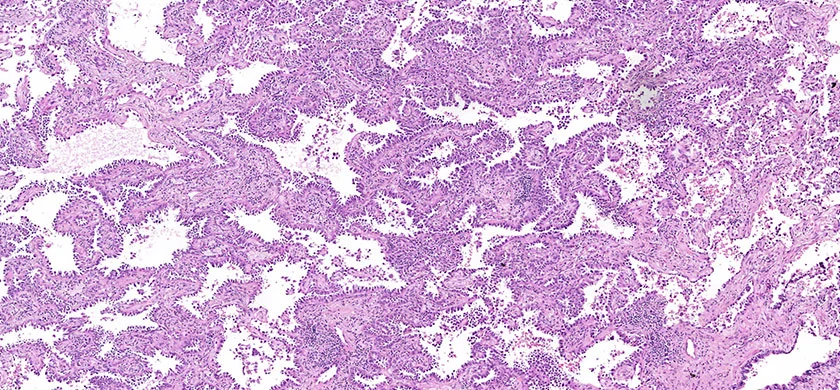

We are happy to announce our new service for our Clients. From the 1st of September, 2020 BioPartners offers you high quality virtual slides (whole slide images) of our banked FFPE samples. Our archive contains more than 1000 scanned images of different types of malignant neoplasms and normal tissues.

Besides, BioPartners offers slide scanning services to medical professionals and organizations at very affordable prices. What you need to do is to send us your glass slides with the completed order form and you will get them back along with the high-resolution and extra-quality virtual slides. Digital slides are either delivered on a DVD (in case of 1-2 glass slides) or an external hard drive. The slide viewing software will be provided as well. Scan type: illumination – bright field, objective magnification – 20x. Approximate size of the digital slide will be between 700MB and 2.5Gb. On your request, your FFPE (formalin fixed, paraffin embedded) or TMA tissue sample can be microtomed and H&E stained.